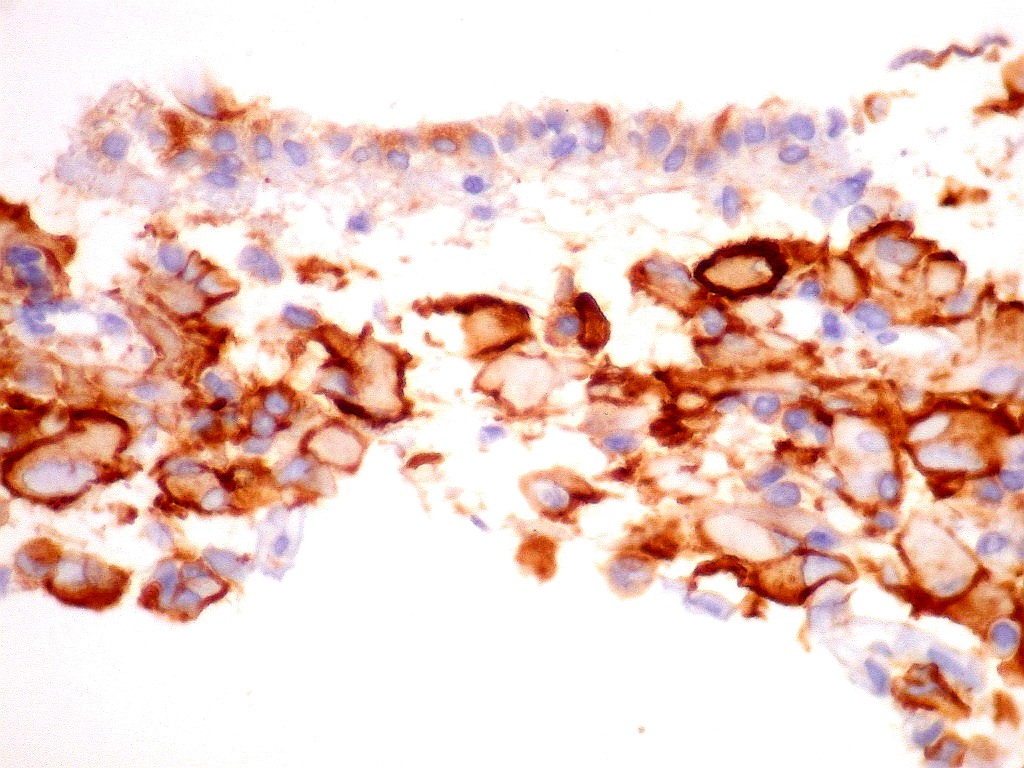

Sinaptofisina.     SNF, um marcador de neurônios, foi positiva no citoplasma em parte das células neoplásicas deste ATRT, enfatizando a expressão multifenotípica dos antígenos neste tumor.

Células  SNF negativas.